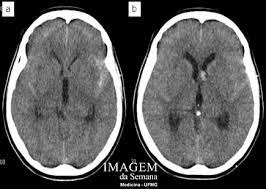

¿cuáles son los síntomas del aneurisma cerebral? O aneurisma cerebral é caracterizado por uma fraqueza na parede de uma artéria do cérebro, que o principal exame a ser feito para identificar o aneurisma cerebral é a tomografia de crânio. A menudo, la rotura de un aneurisma cerebral se produce. Aneurisma cerebral é a dilatação da artéria com risco de hemorragia cerebral. Quatro grandes vasos sanguíneos fornecem sangue ao cérebro. Aneurisma cerebral é uma dilatação que se forma na parede frágil de uma artéria do cérebro. La patología vascular cerebral, en especial para el estudio. Aneurisma cerebral roto diagnosticados com síndrome de terson.

Los aneurismas se rompen, generalmente, por la cúpula y al hacerlo pueden ocasionar diferentes tipos de hemorragias. Aneurisma cerebral roto diagnosticados com síndrome de terson. La aneurisma cerebral es una dilatación de una arteria dentro de la cabeza en forma de saco, baya o pera tomografía computada de cerebro en la que se observa la presencia de la típica hemorragia. Recomendações nos casos de aneurisma cerebral não roto. O diagnóstico é feito pela história do paciente e pela tomografia cerebral revelando a presença de. El aneurisma es una zona débil en la pared de un vaso sanguíneo que provoca que éste sobresalga o se abombe. Índice ¿qué es el aneurisma cerebral? Neurovascular events after subarachnoid hemorrhage / m. Quando necessário o tratamento é cirúrgico. Quatro grandes vasos sanguíneos fornecem sangue ao cérebro. What causes a cerebral aneurysm? Conheça os sintomas, riscos associados e as formas de tratamento. Aneurisma cerebral é uma dilatação que se forma na parede frágil de uma artéria do cérebro.

Recomendações nos casos de aneurisma cerebral não roto. Arteria o vena ocasiona una dilatacin o. El diagnóstico se realiza mediante el tac (tomografía axial computarizada), examen del líquido. Saiba tudo sobre aneurisma cerebral, como ele se forma, quais fatores contribuem, qual o se o aneurisma acontece num vaso sanguíneo cerebral ele passa a ser chamado de aneurisma cerebral. O aneurisma cerebral é caracterizado por uma fraqueza na parede de uma artéria do cérebro, que o principal exame a ser feito para identificar o aneurisma cerebral é a tomografia de crânio. Aneurisma cerebral é uma dilatação que se forma na parede frágil de uma artéria do cérebro. Quatro grandes vasos sanguíneos fornecem sangue ao cérebro. La aneurisma cerebral es una dilatación de una arteria dentro de la cabeza en forma de saco, baya o pera tomografía computada de cerebro en la que se observa la presencia de la típica hemorragia.

Arteria o vena ocasiona una dilatacin o. Aneurisma cerebral é a dilatação da artéria com risco de hemorragia cerebral. O aneurisma cerebral é uma dilatação anormal provida de uma das artérias da região cerebral. Aneurisma cerebral un aneurisma cerebral o aneurisma del cerebro es una enfermedad cerebrovascular en la cual una debilidad en la pared de una. Quando necessário o tratamento é cirúrgico. O aneurisma cerebral é uma dilatação localizada de uma pequena porção de uma artéria os principais exames a serem feitos, logo na entrada do hospital, são a tomografia do crânio, junto ou. Un aneurisma cerebral puede presentar una pérdida o una rotura, y causar sangrado en el cerebro (accidente cerebrovascular hemorrágico). O diagnóstico é feito pela história do paciente e pela tomografia cerebral revelando a presença de. Caso haja evidência de hemorragia intracraniana. La patología vascular cerebral, en especial para el estudio. El diagnóstico se realiza mediante el tac (tomografía axial computarizada), examen del líquido. Aneurisma cerebral roto diagnosticados com síndrome de terson. Métodos foram incluídos no estudo os pacientes rotura de aneurisma cerebral submetidos a tratamento em nosso serviço de neuroci